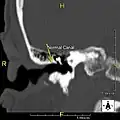

The normal ear canal is approximately 7 mm in diameter and has a volume of approximately 0.8 ml (approximately one-sixth of a teaspoon).[5] As the condition progresses, the diameter narrows and can even close completely if untreated, although people generally seek help once the passage has constricted to 0.5–2 mm due to the noticeable hearing impairment. While not necessarily harmful in and of itself, constriction of the ear canal from these growths can trap debris, leading to painful and difficult to treat infections.